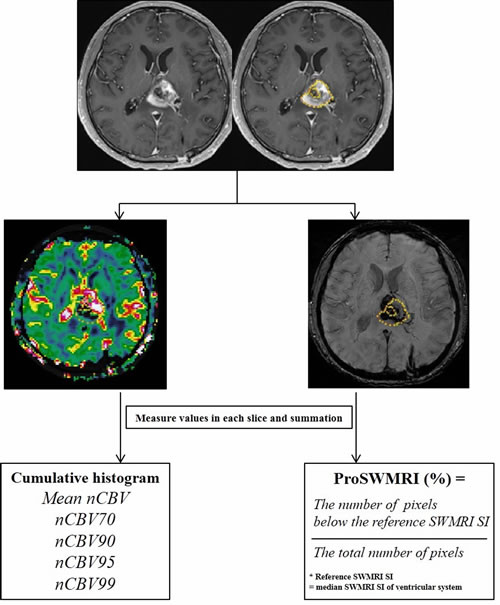

For SWMRI, every pixel value was extracted from each ROI drawn around the entire contrast-enhanced region for each transaxial section. Among four different sets of images generated by Siemens scanner, we utilized the processed SWMRI magnitude image created by combining the phase and the magnitude map [15]. To define the reference signal intensity (SI), the ROI was placed in the ventricular system of the SWMRI map where the median SI was calculated. The proportion of dark SI of the lesions on SW images (proSWMRI) was defined as the percentage of the pixels with values below the reference SI (100 x the number of the pixel with values below the reference SI / the total number of the extracted pixel) [44]. A summary flow chart of the quantitative image analysis is described in Figure 6.

Figure 6: Flow chart of quantitative image analysis. Region of interest (ROI) was manually selected in each section of the enhancing lesions and was semi-automatically co-registered with the normalized relative cerebral blood volume map (nCBV) and susceptibility-weighted magnetic resonance imaging sequences (SWMRI) map. The volume of interest was determined by the summation of each slice; nCBV values and SWMRI values for the entire enhancing lesion were obtained. Cumulative histogram analysis was performed for whole nCBV values. In the cumulative nCBV histograms, mean nCBV, and the 70th, 90th, 95th and 99th percentile points (nCBV70, nCBV90, nCBV95 and nCBV99, respectively) were derived. For SWMRI values, by setting the median SWMRI SI of the ventricular system as the reference, the proportion of SWMRI (proSWMRI) was calculated by dividing the number of pixels below the reference SWMRI SI by the total number of pixels. Note: ROI = region of interest, SWMRI = susceptibility-weighted magnetic resonance imaging sequences, SI = signal intensity, CBV = cerebral blood volume, the Xth percentile point = point at which X% of the voxel values that form the histogram are found to the left of the histogram.